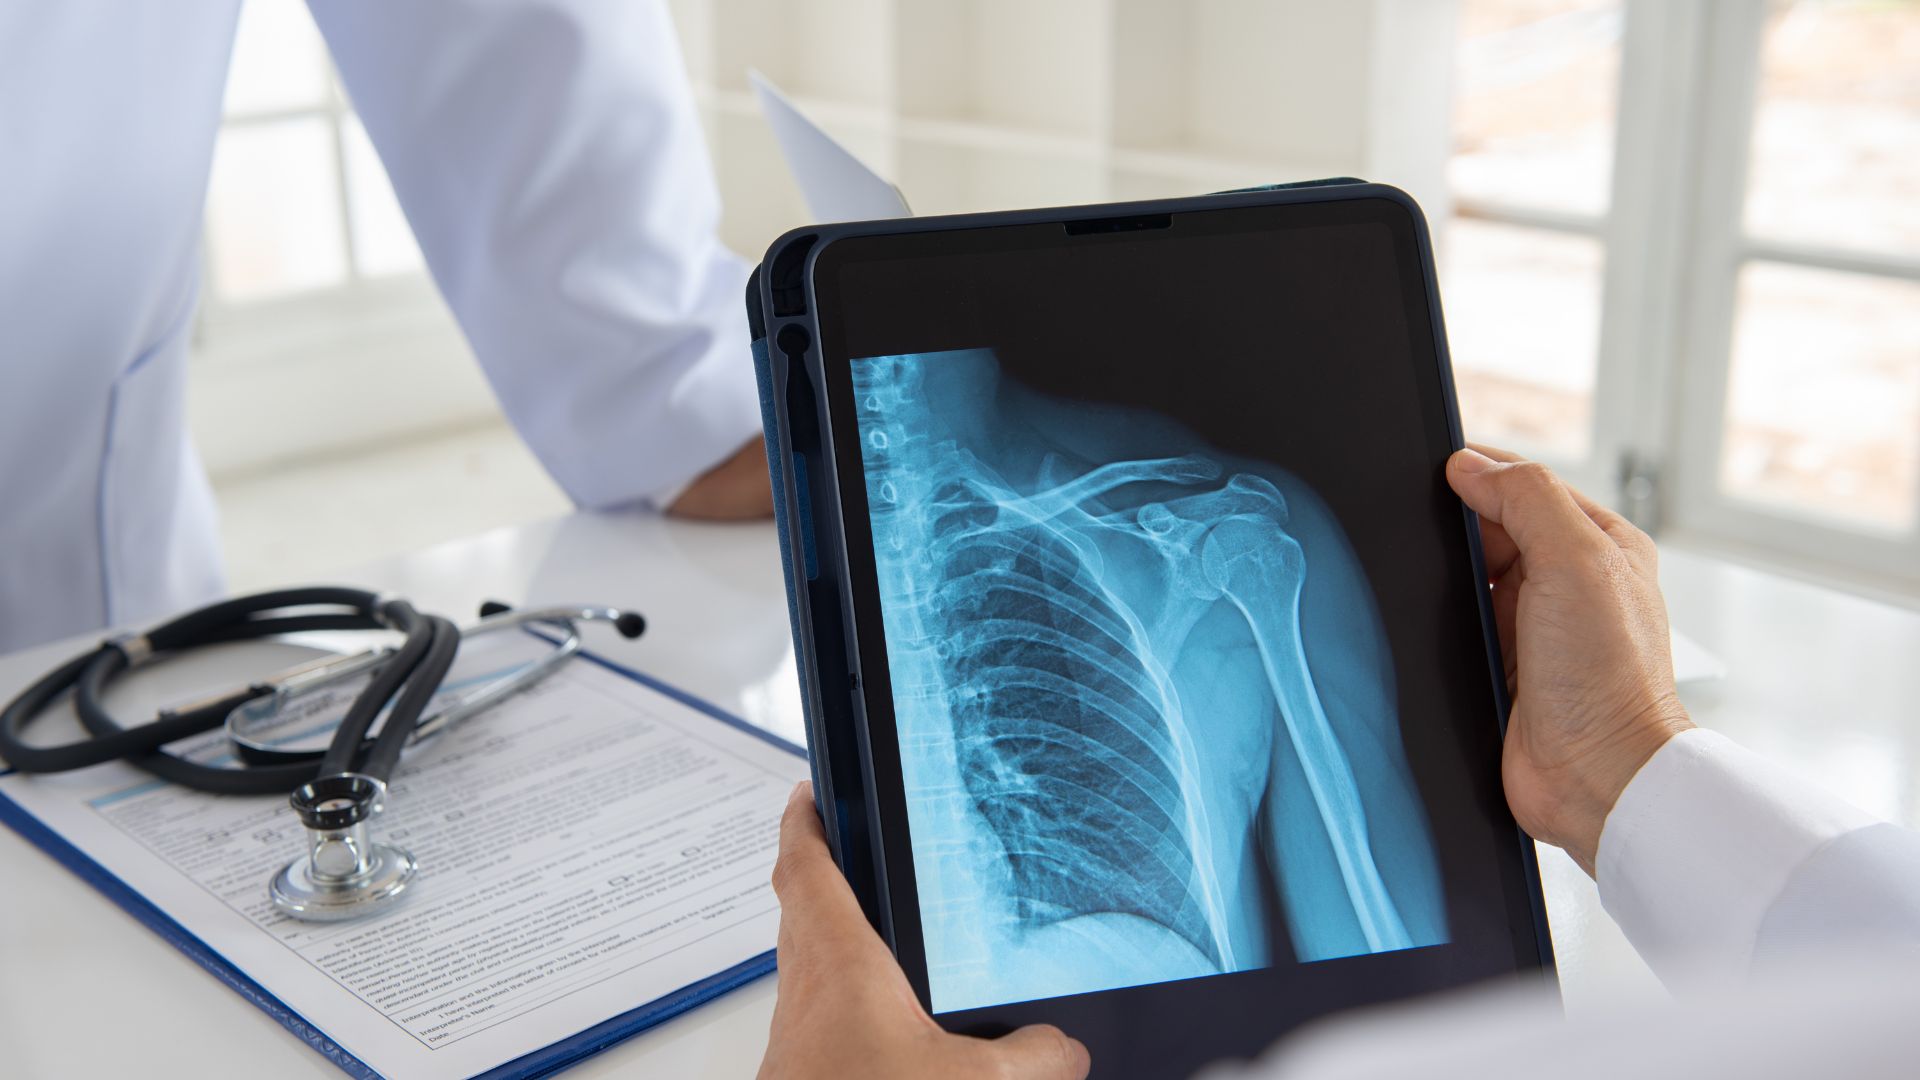

Định vị và thực hiện các tư thế chụp

Kỹ thuật viên sẽ hướng dẫn người bệnh đứng hoặc ngồi đúng tư thế. Các tư thế phổ biến gồm thẳng (AP), nghiêng hoặc tư thế đặc biệt nhằm đánh giá rõ cấu trúc khớp. Việc giữ yên trong vài giây khi phát tia là cần thiết để tránh nhiễu ảnh.

X-quang khớp vai thường được chỉ định khi có chấn thương, đau vai cấp tính nghi ngờ tổn thương xương, đau mạn tính liên quan thoái hóa hoặc cần theo dõi sau điều trị. X-quang là phương tiện chẩn đoán hình ảnh cơ bản, nhanh chóng và hiệu quả trong đánh giá cấu trúc xương khớp vai. Tuy nhiên, việc chỉ định cần dựa trên thăm khám lâm sàng của bác sĩ chuyên khoa nhằm tránh lạm dụng và đảm bảo an toàn cho người bệnh.